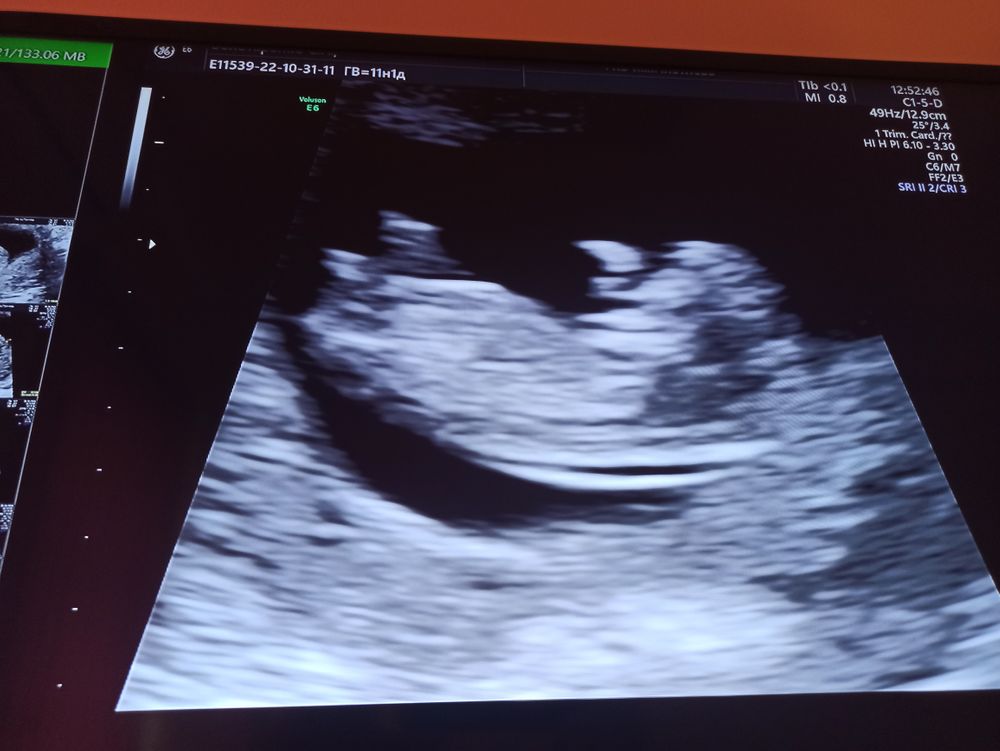

Девочки всём привет! Скажите мне пожалуйста у кого такое было! Сегодня пришла на первый скрининг 11недель и 1 день!(открыла запись сама врач) с врачом по учёту я ещё не виделась приём только 7 числа! На УЗИ не чего не сказали но лицо у неё не довольное, результатов не дали? Только сказали что развитие соответствует 11 неделям и 1 дню! Малыш двигается !ей не понравилось чс 174-176 где то сказала через неделю переделать! Сказала что если что то в крови будет то позвонят! Больше не какой информации не чего! На кушетки от страха трясло! Как теперь успокоиться может у кого такое было! Фото дали только такое сфоткать (((